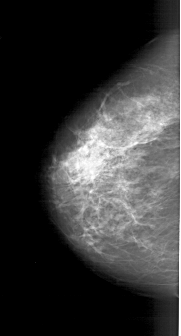

A_1771_1.LEFT_CC

LEFT_CC LINES 5371 PIXELS_PER_LINE 2881 BITS_PER_PIXEL 12 RESOLUTION 43.5 NON_OVERLAY